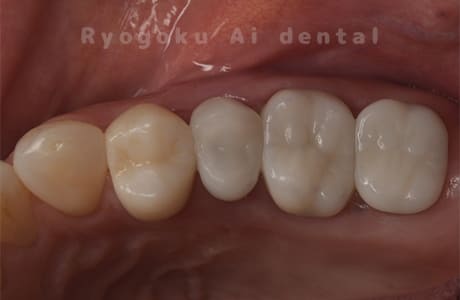

Case07

-

- 原因

- 右下6番歯根破折

- 治療内容

- インプラント治療

- 治療費用

- 約600,000円

右下の腫れが治らないとの事でご来院された患者様です。歯が割れていたため、抜歯を行い、骨に代わるお薬を入れ、インプラントを埋入致しました。経過良好で大変満足していただけました。

<リスク・副作用>

治療後、痛みや違和感、出血、腫れなどが出る事があります。喫煙者、糖尿病などの方の場合、歯が生着しない場合があります。